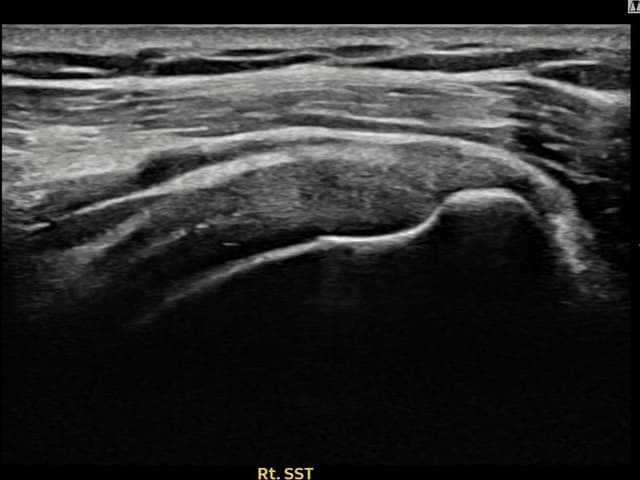

右侧 冈上肌腱 石灰化肌腱炎

10mm × 7mm